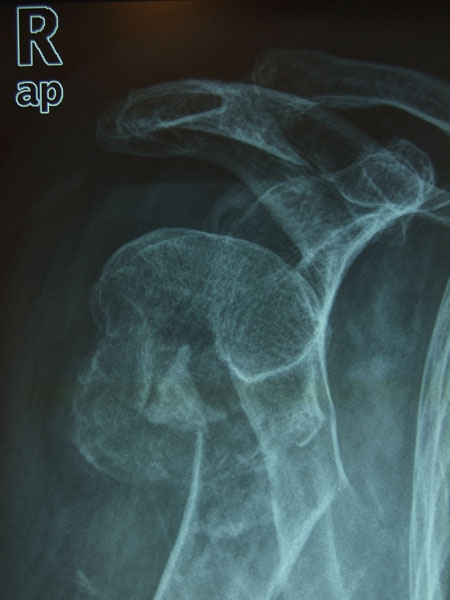

APR Luxación de hombro

Fractura impactada de húmero .